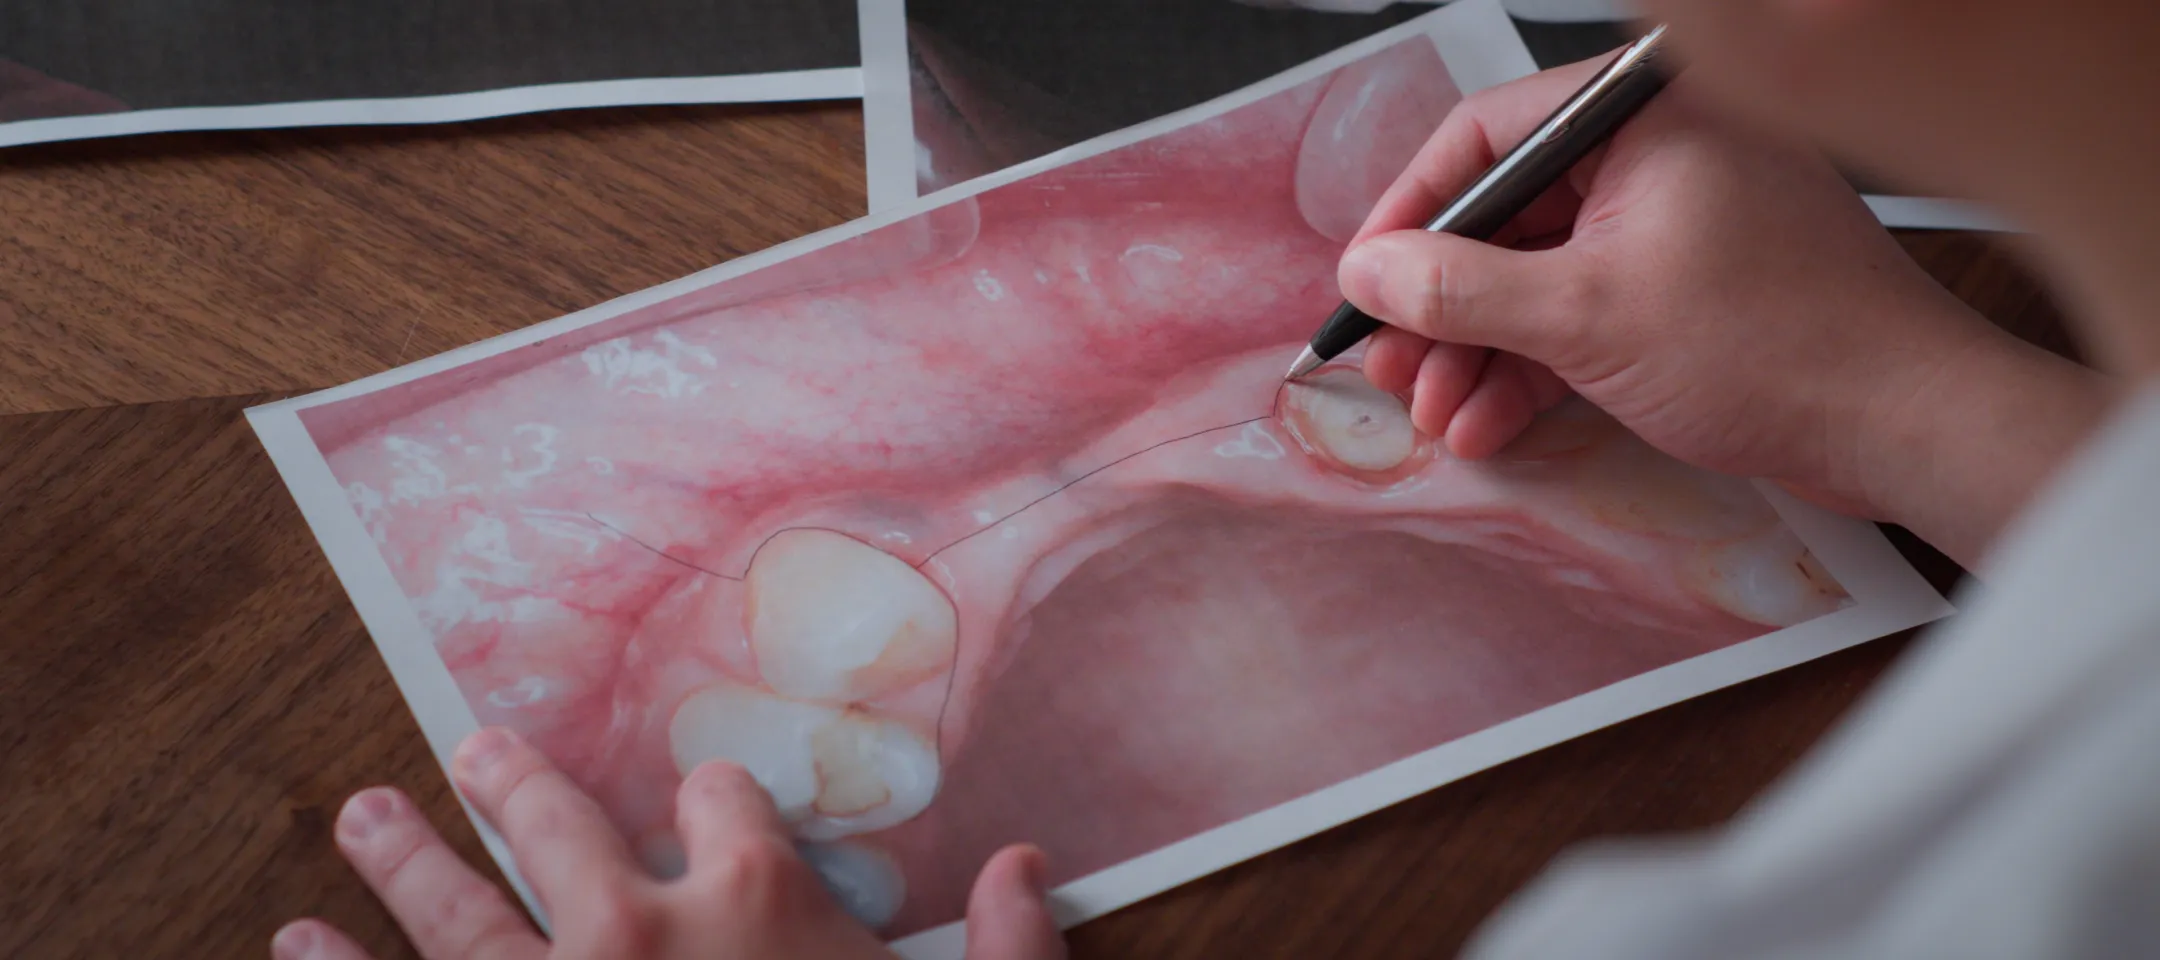

虫歯で多数の歯を失った場合、1本ずつ治療を繰り返すだけでは、噛み合わせや見た目の調和が崩れてしまうことがあります。当院では、CTや口腔内スキャナーを使った全顎的なシミュレーションを行い、噛む力と審美性を両立させる設計を行います。

治療の成功に欠かせないのが、事前の正確な診断です。大杉歯科医院では歯科用CTを用いて、骨の厚みや高さ、神経・血管の位置を三次元で把握します。これにより、インプラントをどの位置・角度で埋入すべきかを精密に計画でき、リスクを最小限に抑えることが可能です。

02審査診断

CTや口腔内スキャナーで骨や歯ぐきの状態を確認し、シミュレーションを実施。サージカルガイドを作製し、精密な治療計画を立てます。